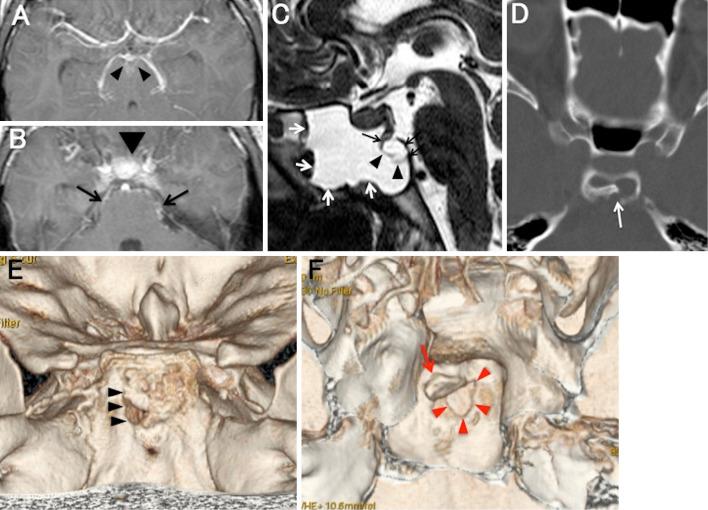

Cases of cerebrospinal fluid (CSF) rhinorrhea due to clival fracture are rare. We present a case of bacterial meningitis with CSF rhinorrhea after a clival fracture. Heavily T2-weighted images showed a bone flap in the thinned clivus and fluid collection in the sphenoid sinus. CSF rhinorrhea developed at 1 month after mild trauma. The fracture may have been caused by the trauma and/or by the pressure gradient between the intracranial CSF space and the sphenoid sinus. A detailed history to identify trauma and an examination to detect bone defects in the skull base are necessary when patients present with bacterial meningitis and persistent rhinorrhea.

因斜坡骨折导致脑脊液鼻漏的病例较为罕见。我们报告一例斜坡骨折后出现细菌性脑膜炎并伴有脑脊液鼻漏的病例。重度T2加权图像显示变薄的斜坡处有骨瓣形成,蝶窦内有液体积聚。轻度外伤后1个月出现脑脊液鼻漏。骨折可能是由外伤和/或颅内脑脊液间隙与蝶窦之间的压力梯度所致。当患者出现细菌性脑膜炎和持续性鼻漏时,详细询问外伤史并检查以发现颅底骨缺损是必要的。